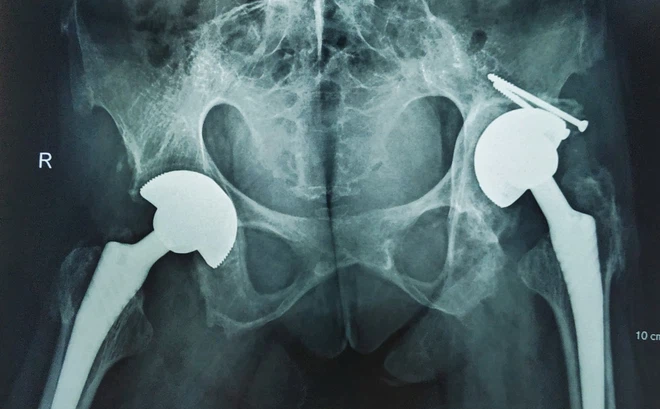

TS.BS Ngô Bá Toàn, Phó trưởng khoa Phẫu thuật Chấn thương chung, Bệnh viện Hữu nghị Việt Đức, cho biết: Ca mổ của bệnh nhân H là một ca mổ vô cùng phức tạp, cả hai khớp háng đã có biến chứng viêm dính biến dạng. Tình trạng viêm trong máu của bệnh nhân thường xuyên ở mức cao sẽ khiến cho vết thương lâu lành, thậm chí nhiễm trùng sau mổ.

Trước tình trạng của bệnh nhân, các bác sĩ đã hội chẩn đa chuyên khoa kỹ lưỡng và đưa đến quyết định mổ thay khớp háng 2 bên bằng kỹ thuật mổ ít xâm lấn.

Các phương pháp điều trị chỉ có thể cải thiện triệu chứng và ngăn ngừa bệnh trở nên xấu đi. Phẫu thuật thay khớp háng được chỉ định trong trường hợp bệnh nhân đau kéo dài, hạn chế vận động và có phá hủy cấu trúc rõ trên hình ảnh X quang. Phẫu thuật chỉnh hình đối với cột sống được chỉ định khi cột sống biến dạng.